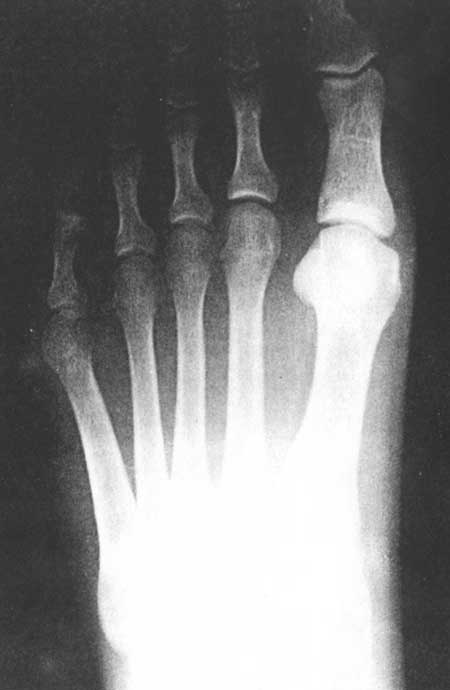

Fig 3C (pre-operative)

|

Fig 3C (post-operative)